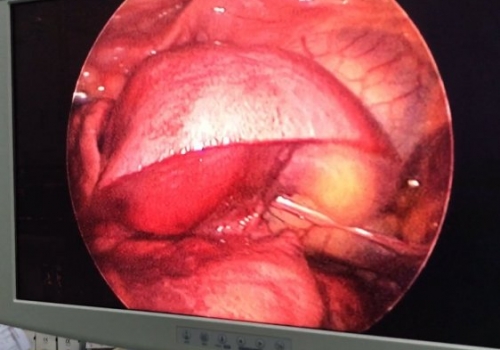

MediastinalTeratoma .Torokoskopik teratomanın eksiziyası

Daha bir çətin əməliyyat 8 yaşlı pasientdə döş boşluğunda törəmə- Ağciyərin orta payı üzərində böyük həcmli törəmə Teratoma. Torokoskopik törəmənin eksiziyası

Dr. Toğrul Ömərov